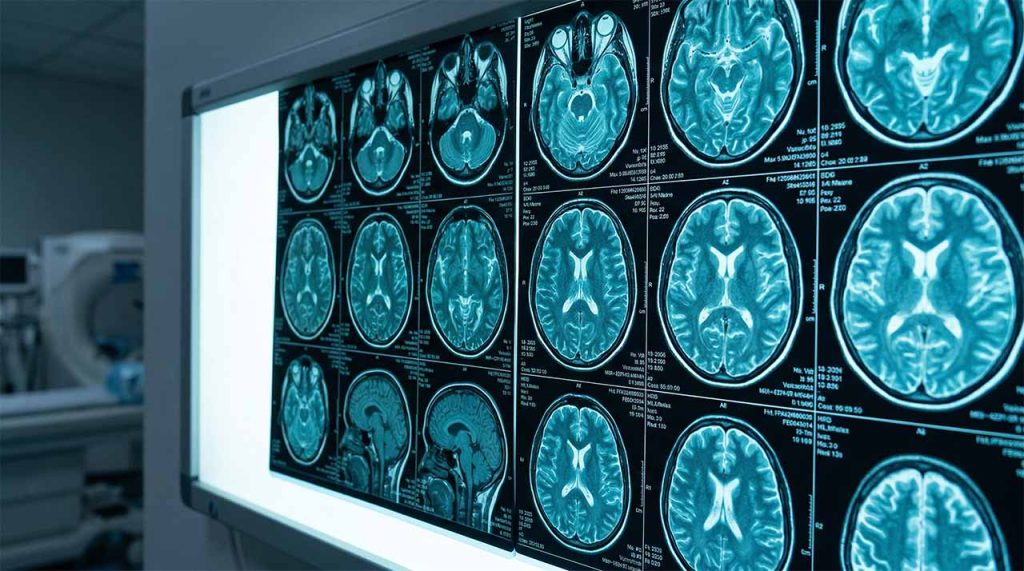

Migraines

If headaches and migraines are persistent, changing in pattern, or accompanied by symptoms such as weakness, visual changes, or numbness, a specialist review can help clarify the cause. In selected cases, minimally invasive techniques may be appropriate.